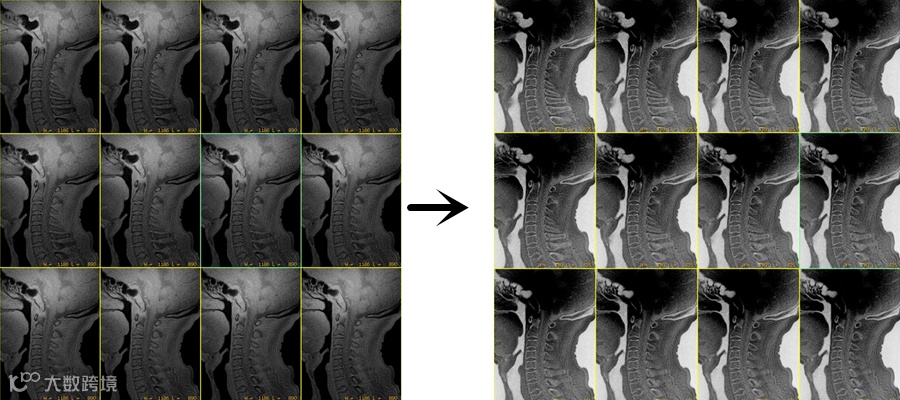

上图△,椎体成像。成像FA =2°,体素1.2*1.2*1.2mm。